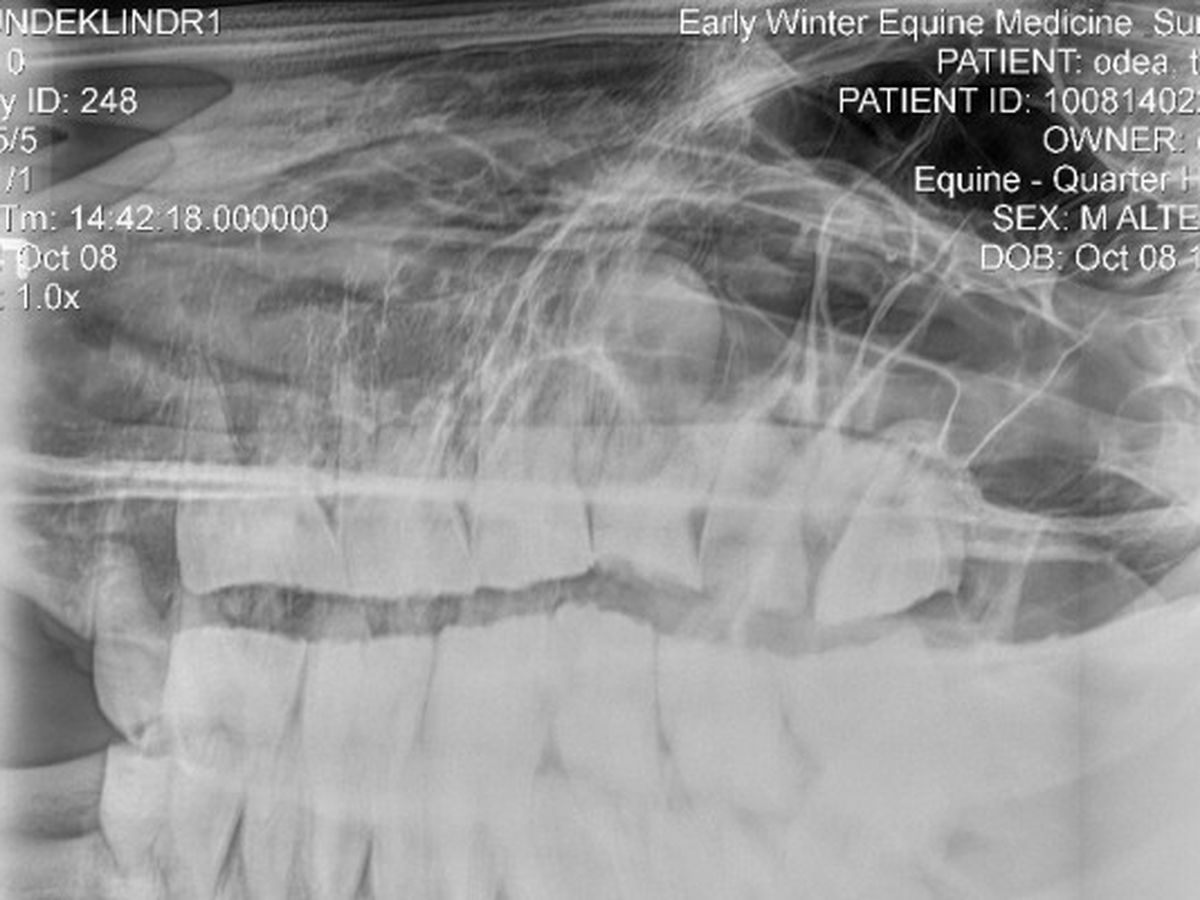

In recent months Topaz has been having sinus discharge on and off. I called Dr. Laura Rath of Midstate Veterinary out and her exam reveled some pretty bad teeth. She touched up what she could to make Topaz comfortable and had to have a specialist come out. Dr. Rebecca Goodale of Early Winter Equine came highly recomended from several sources. Upon her exam and radiographs it's been determined that two broken teeth (one on the left and one on the right) and a few other bad ones on each side are causing the sinus problems. The broken teeth are allowing food to travel into his sinuses and rot there.